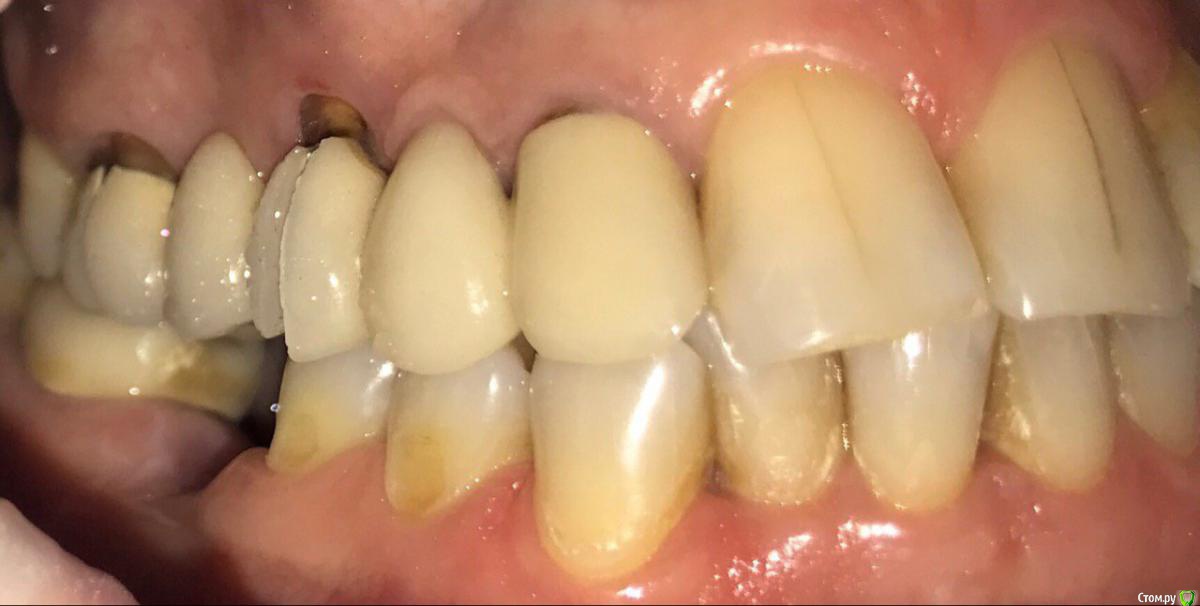

ksenistom Опубликовано 13 декабря, 2016 Поделиться Опубликовано 13 декабря, 2016 Пациентка И.,55 лет,хочет голливуд на обеих челюстях,в виде циркониевых коронок,справа сверху снят мостовидный протез,где установлены 2импл. неделю назад и удалён ретинированный клык в обл 13зуба(фото панорамы нет),поэтому эту сторону пока не трогаем,в области 46 планируется имплантация, 36зуб-вкладка+коронка,в области скученных нижних зубов сделан воксап.Вопрос в том,с чего начать?! Ссылка на комментарий